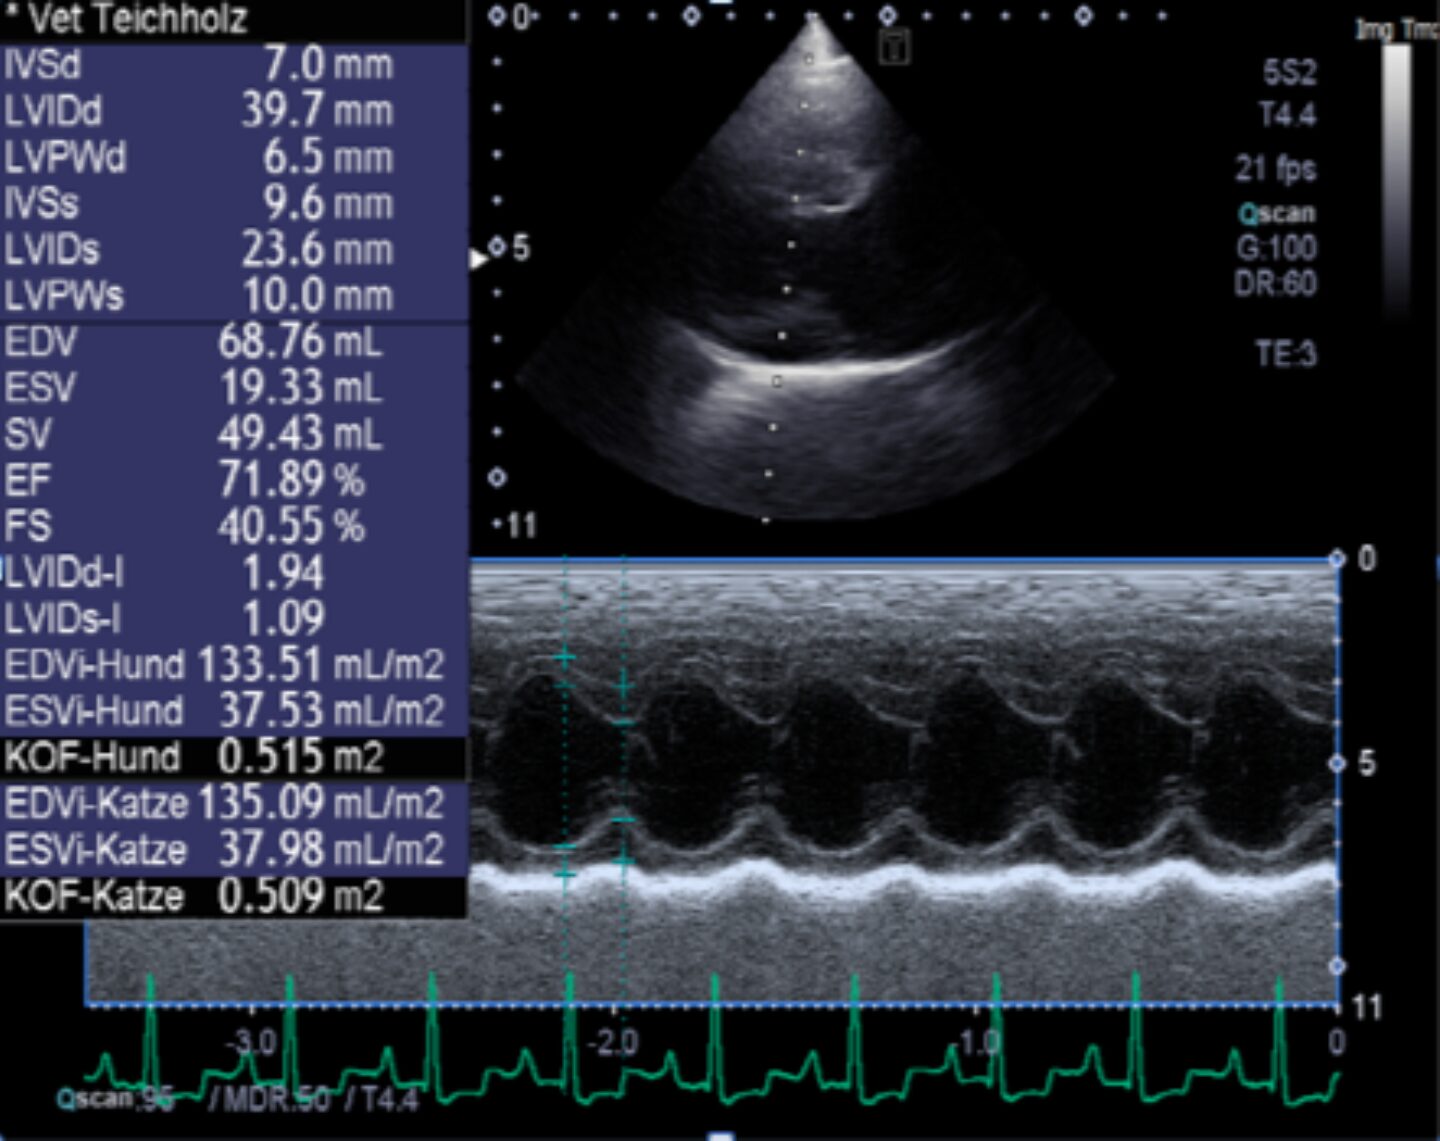

Ultraschall: in der rechtsanliegenden Längsachse sind die linke Kammer und der linke Vorhof vergrößert; die rechten Kammern stellen sich unauffällig dar. Die Mitralklappe ist deutlich degenerativ verändert und prolabiert in den linken Vorhof. Die Maße des linken Ventrikels liegen in der Teichholzuntersuchung diastolisch oberhalb der Norm. LA/Ao liegt im M Mode und im B Bild oberhalb der Norm. In der Farbdoppler-sonographischen Untersuchung stellen sich Turbulenzen über der Mitral- und Trikuspidalklappe dar, die restlichen Flussmuster sind unauffällig Die systolische Funktion des linken Ventrikels ist gesteigert, die diastolische Funktion ist deutlich reduziert, die gemessenen Flussgeschwindigkeiten liegen sämtlich in der Norm. Die Rückflussgeschwindigkeit über der Mitralklappe liegt bei 5,8 m/s, der Rückfluss über der Trikuspidalklappe wird bei 3,0 m/s gemessen.

LVIDd-I

1,9

LVIDs-I

1,1

LA/Ao B-Bild

2,2

LA/Ao M-Mode

2,5